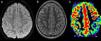

Niña de 9 años con cuadro de disartria, hemiparesia derecha de predominio braquial mantenida durante una hora y sintomatología sensitiva en miembro superior derecho (parestesias) de igual duración, seguida de dolor hemicraneal izquierdo que duró varias horas. Había sucedido un episodio previo leve 2 meses atrás, con parestesias en miembro superior derecho. No existían antecedentes familiares de migraña hemipléjica (MH). Se realizó resonancia magnética (RM) durante la fase aguda para descartar la presencia de anomalías, especialmente isquemia cerebral (fig. 1).

Las imágenes de difusión y de T2 no evidencian alteraciones de señal o morfología, a diferencia de la clara hipoperfusión parietal izquierda, que se normalizó posteriormente. Este hallazgo, reversible en ASL, siendo el resto de secuencias (T2 y difusión) normales, sirve para afianzar el diagnóstico de presunción clínica de MH y excluir otras posibilidades de diagnóstico diferencial.

Parámetros: TE, 28ms; TI, 1.800ms, TI1s, 1.200ms; TI, 2.000ms; TR, 3.000ms; bandwidth: 62,5kHz; flip angle, 90°; FOV, 24; matriz 64×48; grosor: 8mm, sin gap.